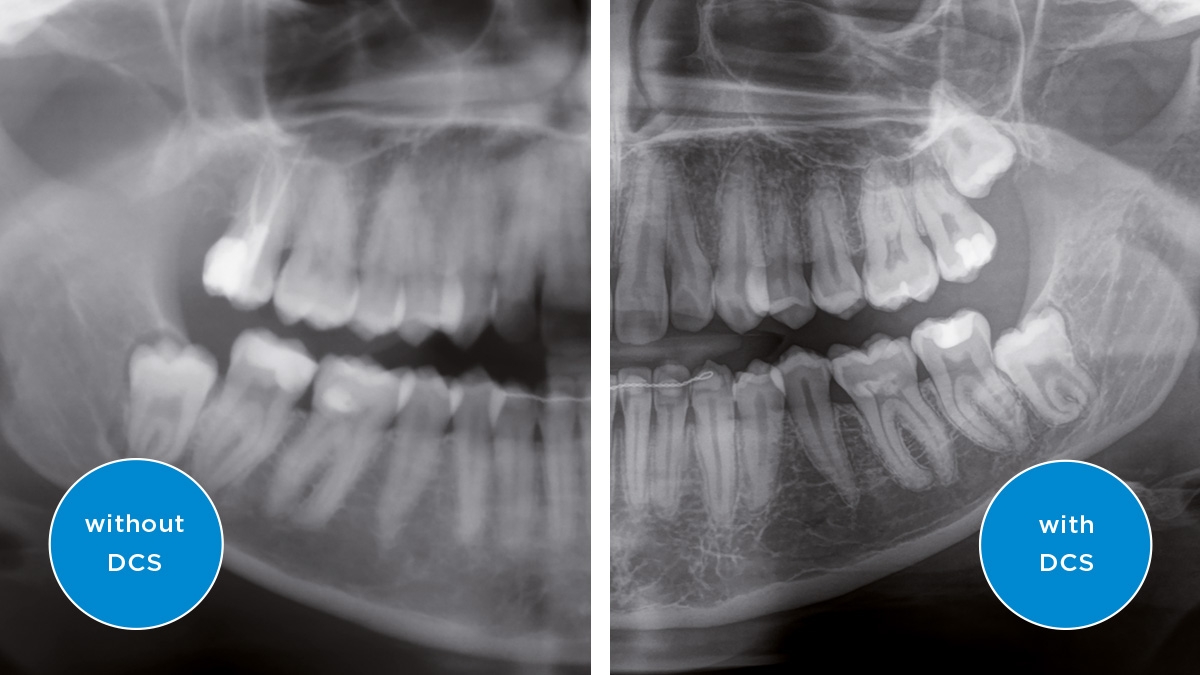

We developed a 10-point concept for easy patient positioning and X-ray imaging. Our concept is primarily about two things: high image quality and comfort for the patient and the assistant. This concept supports and provides the tools needed to ensure high-quality images for treatment analysis and focuses on ergonomics and comfort for the patient and assistant.